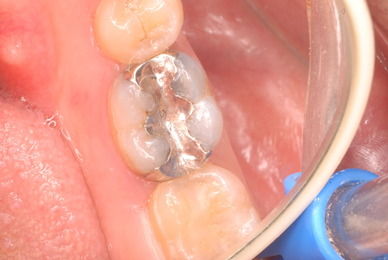

今では染色液がありますから取り残しなど少ないと思われますが、実際に取れたという銀歯を持ってきた患者さんの歯を見ますと、虫歯の取り残しを痛感いたします。

もし取れなくても中で拡がると神経を損傷し、しみるとか最悪の場合神経を取らなくてはならなくなります。

写真は典型的な取り残したまま銀歯を入れていた方のものです。よくぞ痛くならなかったものです。

意外と手間取り一時間以上かかりセメントを入れてとりあえず終了いたしました。神経が近いので傷つけて損傷すると助かる見込みが少なくなり、痛みが出て死んでしまうとか膿んでしまうこともあるのです。![570b1c06-s[1]](https://livedoor.blogimg.jp/netdental/imgs/6/0/60221eb2.jpg)